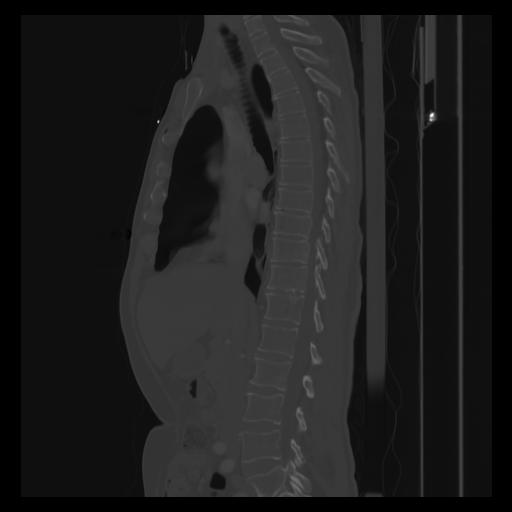

30 CUERPO,CE,Sagittal,3.000,CUERPO,Sagittal,